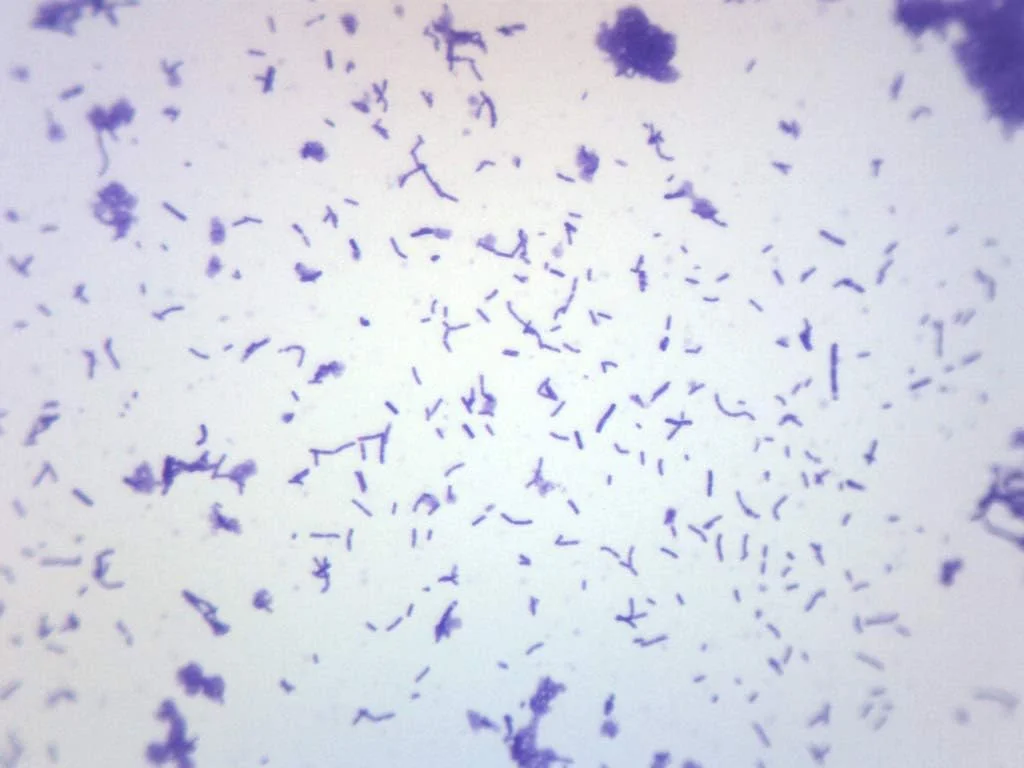

تجهیزات آزمایشگاهی شامل ابزارهایی متنوع با کاربری های بسیار خاص هستند. از تجهیزات پایه ای مانند بیکر، ارلن، پیپت و میکروپیپت گرفته تا دستگاه های پیشرفته ای مانند اسپکتروفتومتر، سانتریفیوژ، انکوباتور، هات پلیت و آون. این تجهیزات از جنس های مقاومی نظیر شیشه بوروسیلیکات، فولاد ضد زنگ یا پلاستیک های خاص ساخته می شوند تا در برابر مواد شیمیایی و دمای بالا مقاوم باشند. ابعاد، ظرفیت، درجه دقت، سرعت عملکرد و مصرف انرژی از ویژگی های مهم فنی این ابزارها به شمار می رود. برخی مدل های تجهیزات آزمایشگاهی دارای صفحه دیجیتال و سیستم های هوشمند کالیبراسیون هستند تا دقت اندازه گیری ها را به حداکثر برسانند.

استفاده از تجهیزات آزمایشگاهی استاندارد باعث کاهش خطاهای انسانی، افزایش دقت و سرعت عمل در آزمایش ها می شود. این تجهیزات از متریال های مقاوم و بادوام تولید شده اند و طول عمر بالاتری دارند. همچنین بسیاری از آن ها مجهز به سیستم های ایمنی مانند قطع خودکار، هشدار دما یا خطای کاربری هستند که از بروز خطرات احتمالی جلوگیری می کند. در مقابل، نمونه های غیراستاندارد ممکن است دقت کافی نداشته باشند، خراب شوند یا حتی خطراتی برای کاربر ایجاد کنند. انتخاب تجهیزات با کیفیت، تضمینی برای عملکرد مستمر و قابل اتکا در محیط های حساس آزمایشگاهی است.